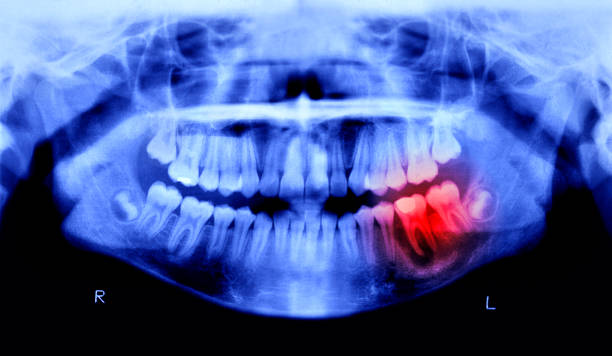

Prompt Examination & Diagnosis

We assess the source of pain with X-rays or visual checks and explain the issue clearly.